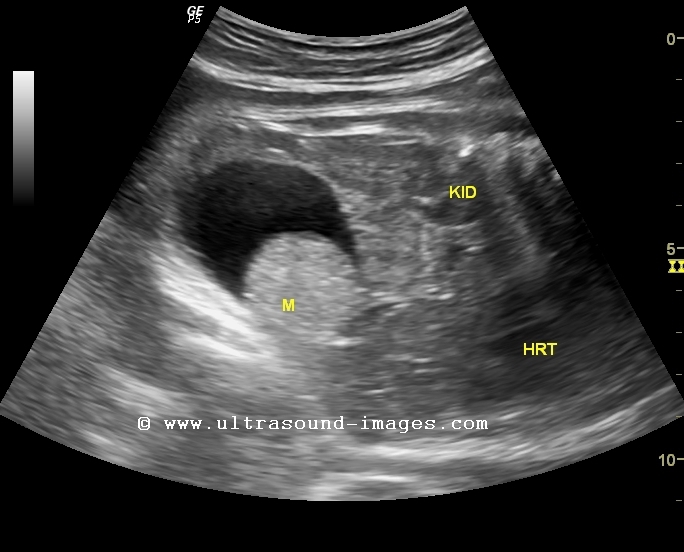

This 34 week fetus shows a large cystic lesion (4.5 cms.) arising from the pelvis with a solid, echogenic rounded mass within it (see ultrasound images above). This is the typical sonographic appearance of a sebum plug within a mature cystic teratoma or dermoid cyst. In ultrasound images above, ST= stomach, LK= left kidney, BL= fetal urinary bladder, M= mass.